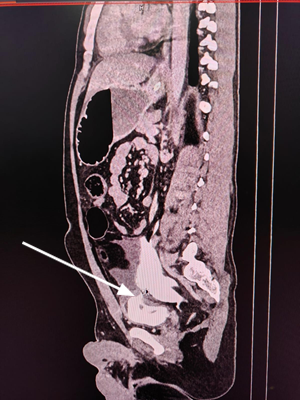

Ultrasonography whole abdomen revealed free fluid

with internal echoes in the pelvis. CECT abdomen(being

the investigation of choice for blunt trauma abdomen) revealed gross spillage

of dye from the bladder into the peritoneum suggestive of intraperitoneal

bladder rupture as depicted in figure 2 (arrowhead). No other visceral injury

was seen. Gross free fluid was noted in the peritoneum.

Figure 2. CECT whole abdomen with pelvis showing

contrast extravasation from the bladder into the peritoneal cavity.

In

our patient abdomen was distended with generalized tenderness and guarding

along with gross hematuria was present on catheterization.CECT's

whole abdomen revealed rupture of the bladder dome along with extravasation of

contrast into the peritoneal cavity. So, the patient was immediately taken up

for exploratory laparotomy, and bladder repair was done.